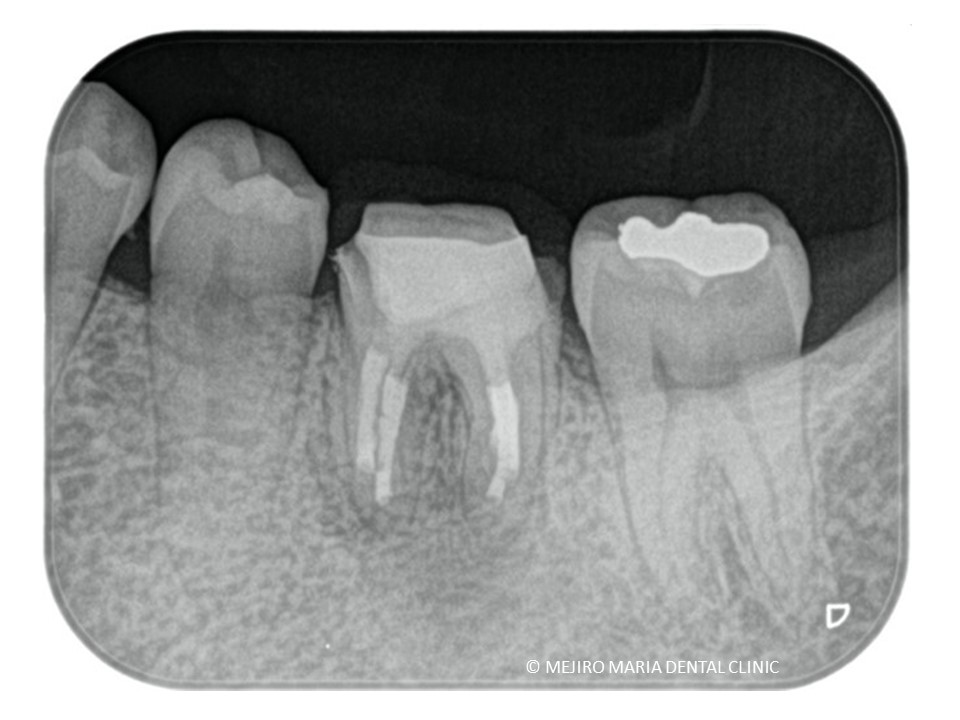

2年以上他院にて根管治療で通院されていた患者様の症例です。長期間通院したにもかかわらず症状は改善されず抜歯の宣告をされ、当院を受診されました。

左下6番直下は大きく腫脹し、サイナストラクト(瘻孔・フィステル)と言われる排膿路が確認できました。

当院にて再根管治療を施すもサイナストラクト(瘻孔・フィステル)の消失は確認できず、予後不良と判断し歯根端切除術を行った。

歯根端切除術を施した後にはサイナストラクト(瘻孔・フィステル)の消失が確認でき、根尖性歯周炎は寛解へ向かっていると考えられます。

今後、最終補綴処置を行い最低2年のフォローアップ(経過観察)を行い、レントゲンで注意深く根尖周囲組織の治癒を確認していきます。